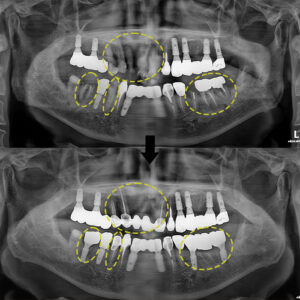

모든 치료가 마무리 된 후의 사진이에요❗

전, 후 사진을 보시면 부러져 있던 치아들이

임플란트나 보철치료로

회복된 모습을 볼 수 있어요.